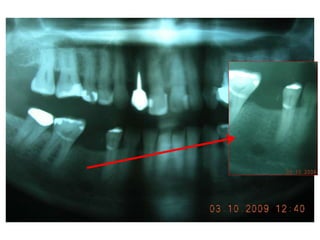

Dogmar Dasgupta,March,2009

Immediately after operation

On 11th.March,2009.

2

9

April,2012